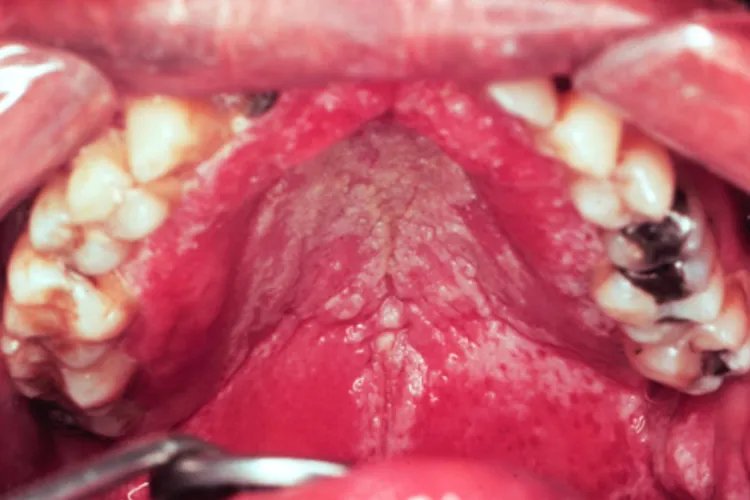

口腔白色念珠菌图片

的有关信息介绍如下:概述口腔白色念珠菌一般指口腔出现白色念珠菌感染,患者表现为口腔黏膜出现白色斑块。口腔白色念珠菌感染多见于鹅口疮、义齿性口炎、念珠菌性口角炎等,是真菌感染性疾病。症状口腔出现白色念珠菌感染多见于鹅口疮、义齿性口炎、念珠菌性口角炎等疾病,症状表现有所差异。鹅口疮鹅口疮表现为口腔黏膜表面覆盖白色乳凝块样小点或小片状物,可逐渐融合成大片白斑,不易擦去,周围无炎症反应,强行剥离后局部黏膜潮红、粗糙,可有溢血,不痛、不流涎。